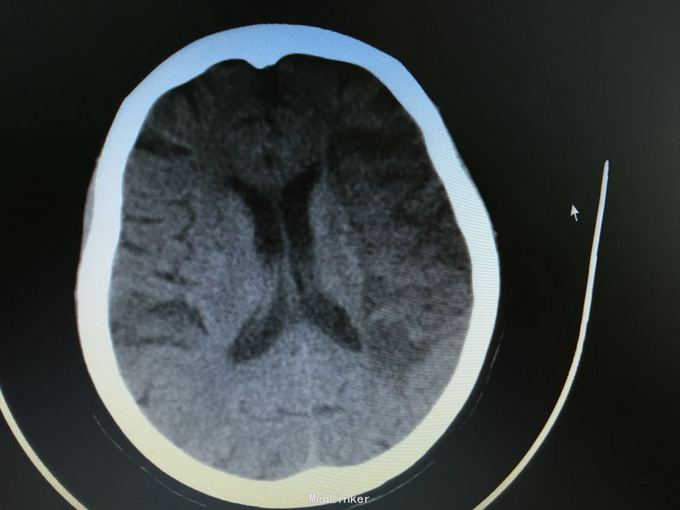

主诉:突发左侧肢体无力伴意识障碍2.5小时。 现病史:患者于2.5小时前突发左侧肢体无力,左侧肢体完全不能动,伴有意识障碍,急诊头CT显示多发脑梗死,为进一步诊治入院。 既往史:高血压,冠心病支架后,阵发房颤。

昏睡,完全混合性失语,双眼向左侧凝视,右侧肢体肌力0级,右侧病理征阳性。 头CT见多发陈旧小梗死。

诊断:大脑半球大面积脑梗死 治疗:抗血小板,脱水,降脂等,抗凝预防下肢静脉血栓

目前住院10余天,意识清楚,但仍遗留左侧肢体肌力0级,混合性失语等严重功能残疾。复查CT显示为左侧大脑半球大面积脑梗死。 讨论:对于高龄,大面积脑梗死患者,时间窗内是否溶栓?静脉还是动脉溶栓?